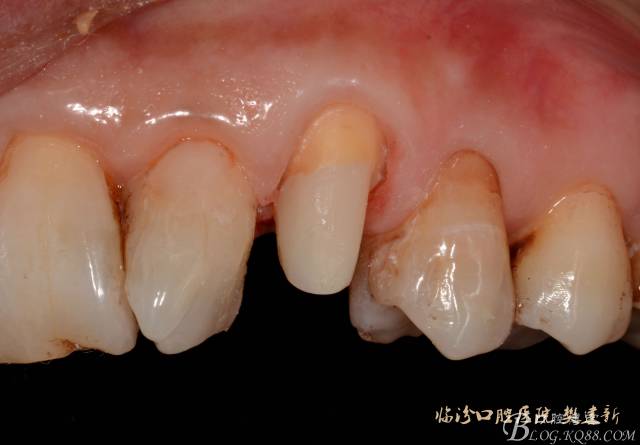

圖5  置纖維樁樹脂樁備牙后情況

640 (4).jpg